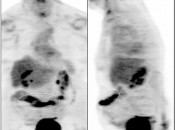

Metformin:

This very popular medication is notorious for causing extensive and extremely intense bowel uptake (colon > small bowel). As this uptake can occasionally limit interpretation, we ask our patients to discontinue Metformin 24-hours prior to their exam.